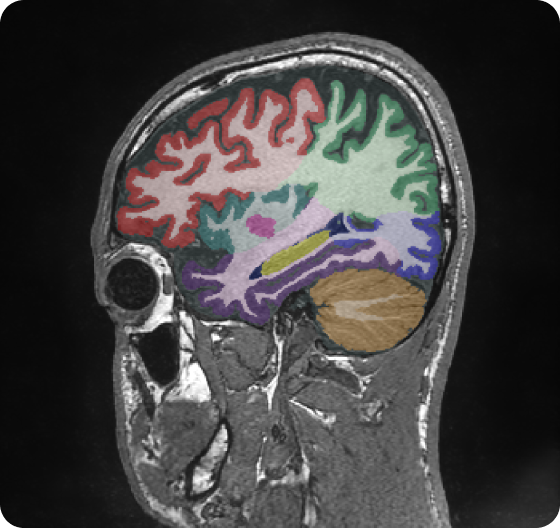

Retrospective brain volumetric analysis in a female patient diagnosed with Alzheimer’s disease at age 77 showed progressive brain atrophy over a 5-year period. The scans demonstrate temporal cortical atrophy with marked ex-vacuo enlargement of the lateral ventricles.

PATIENT

Female patient diagnosed with Alzheimer's Disease at Age 77

Analysis period

5 years

regions of interest

Temporal cortex

Hippocampus

Inferior lateral ventricles

Age 72

Age 74

Age 77

Lateral ventricle